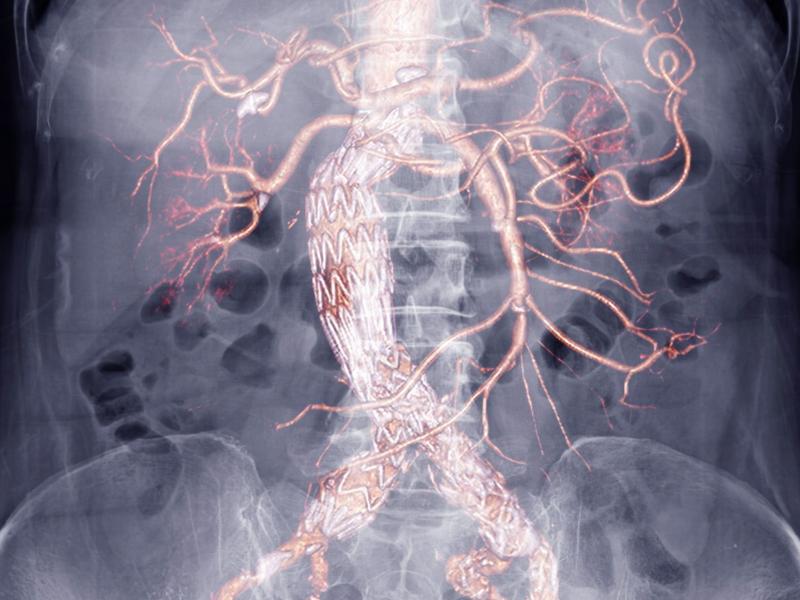

Καρδιολόγος προειδοποιεί: Οι 4 εξετάσεις που αποκαλύπτουν αν έχετε φραγμένες αρτηρίες

Καρδιολόγος εξηγεί ποιες τέσσερις εξετάσεις μπορούν να εντοπίσουν το πρόβλημα εγκαίρως, προλαμβάνοντας σοβαρές επιπλοκές όπως έμφραγμα ή εγκεφαλικό.

Καρδιολόγος προειδοποιεί: Οι 4 εξετάσεις που αποκαλύπτουν αν έχετε φραγμένες αρτηρίες